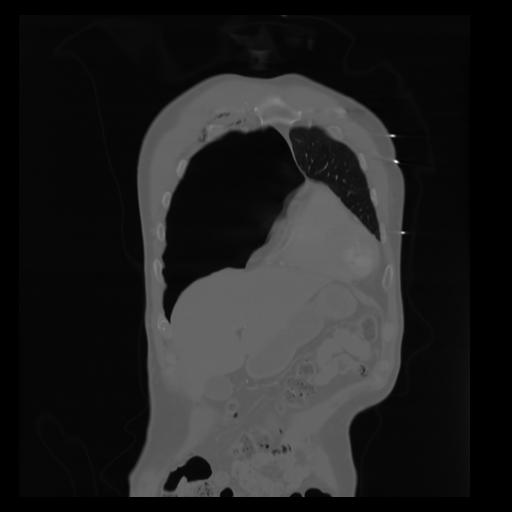

29 CUERPO,CE,Coronal,3.000,CUERPO,Coronal,